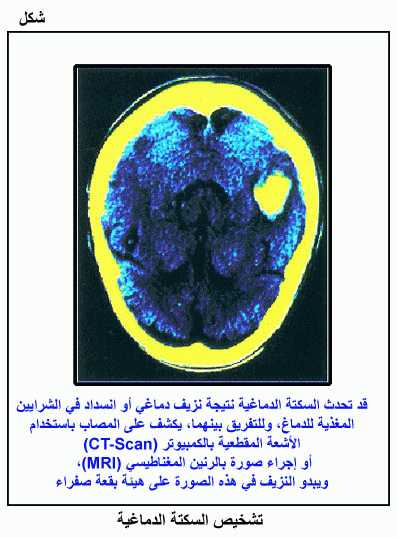

تشخيص السكتة الدماغية